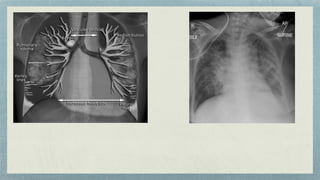

Position:- Superior Vena Cava/ Cavoaortal

Position:- Main or Lobar pulmonary artery

In the pulmonary artery

In the left pulmonary artery

In right pulmonary artery

Wedge shaped opacity C/L lung collapse